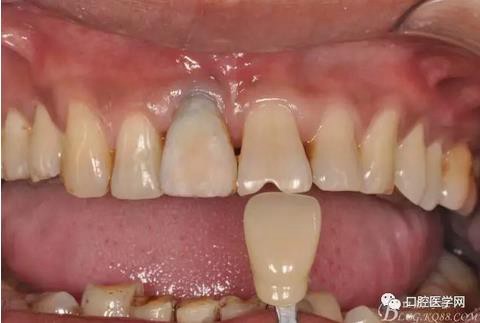

圖13 比色

圖14 烤瓷冠模型唇側(cè)照

圖19 口內(nèi)修復(fù)基臺正位照

圖20 口內(nèi)修復(fù)基臺正位照